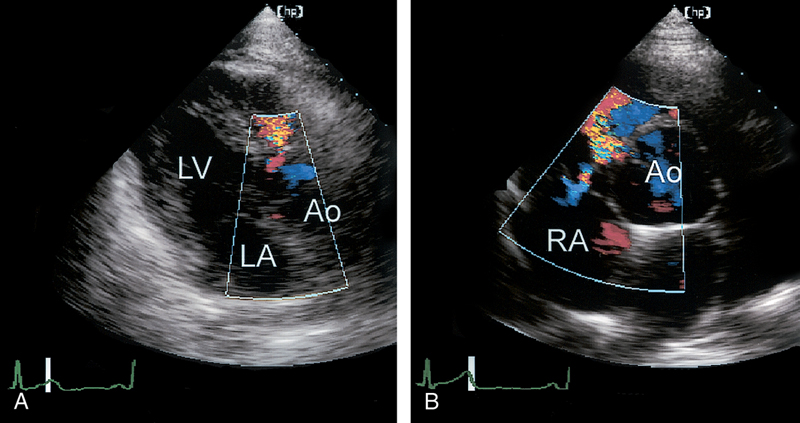

فحوصات تشخيصية لبعض امراض القلب والشرايين التاجية